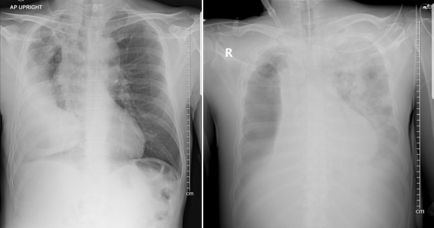

ภาพถ่ายรังสีทรวงอก (chest radiography) มักแสดงลักษณะที่ไม่จำเพาะเจาะจง โดยมากมักต้องอาศัยลักษณะอาการและภาพถ่ายรังสีทรวงอกเก่าเปรียบเทียบ โดยอาจพบการเปลี่ยนแปลงหรือหายไปของน้ำในช่องเยื่อหุ้มปอด (pleural effusion) (ดังรูปที่ 1) หรือพบลักษณะของฟองอากาศ (air bubbles) เกิดขึ้นใหม่ภายในโพรงน้ำในช่องเยื่อหุ้มปอด โดยอาจเห็นร่วมกับการเกิดเงาฝ้าขึ้นใหม่ในปอดส่วนอื่น (ดังรูปที่ 1)

เป็นภาพถ่ายรังสีทรวงอกเดิม แสดงให้เห็นโพรงน้ำในช่องเยื่อ หุ้มปอดด้านขวาที่มีอยู่เดิม ขวา

เป็นภาพถ่ายรังสีทรวงอกใหม่ แสดงให้เห็นถึงการหายไปของน้ำในช่องเยื่อหุ้มปอดด้านขวา โดยมีลมเข้ามาแทรกแทน ร่วมกับเกิดเงาฝ้าขึ้นใหม่ในปอดด้านซ้าย